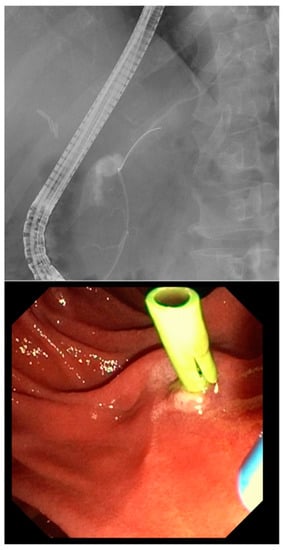

Only in four patients, the abdominal drain inserted intraoperatively, were removed before the onset of symptoms (in average four weeks). The remaining patients already underwent PCD before an EUS-guided drainage was approached. When transmural drainage was achieved, PCD was either removed or, in case of infection, kept in place for irrigation. Technical success was achieved in 96% owing to one case of LAMS maldeployment during EUS-guided intervention. All LAMS were removed within a period of 6–8 weeks. If needed, a double pigtail was kept in place to further facilitate a continuous drainage (Figure 2). The mean time until fistula closure was 2.7 (range 2.1–5.3) months, keeping in mind that transmural stenting was mainly approached in settings of refractory fistulas.

Figure 2. EUS showing a fluid collection and endoscopic view on a LAMS plus a double pigtail.